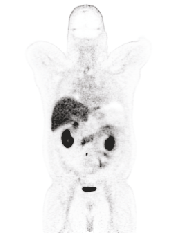

Position emission tomography (PET) is widely used in clinics and research due to its quantitative merits and high sensitivity, but suffers from low signal-to-noise ratio (SNR). Recently convolutional neural networks (CNNs) have been widely used to improve PET image quality. Though successful and efficient in local feature extraction, CNN cannot capture long-range dependencies well due to its limited receptive field. Global multi-head self-attention (MSA) is a popular approach to capture long-range information. However, the calculation of global MSA for 3D images has high computational costs. In this work, we proposed an efficient spatial and channel-wise encoder-decoder transformer, Spach Transformer, that can leverage spatial and channel information based on local and global MSAs. Experiments based on datasets of different PET tracers, i.e., $^{18}$F-FDG, $^{18}$F-ACBC, $^{18}$F-DCFPyL, and $^{68}$Ga-DOTATATE, were conducted to evaluate the proposed framework. Quantitative results show that the proposed Spach Transformer can achieve better performance than other reference methods.